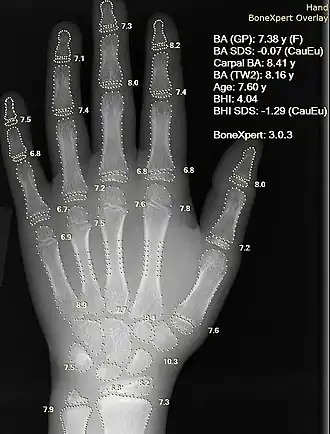

Image and sound processing

Information can take the form of images, sound, video or other multimedia. Bits of information can be streamed via signals. Its processing is the central notion of informatics, the European view on computing, which studies information processing algorithms independently of the type of information carrier – whether it is electrical, mechanical or biological. This field plays important role in information theory, telecommunications, information engineering and has applications in medical image computing and speech synthesis, among others. What is the lower bound on the complexity of fast Fourier transform algorithms? is one of the unsolved problems in theoretical computer science.

|

|

|

|

|

|

| FFT algorithms | Image processing | Speech recognition | Data compression | Medical image computing | Speech synthesis |

Computational science, finance and engineering

Scientific computing (or computational science) is the field of study concerned with constructing mathematical models and quantitative analysis techniques and using computers to analyze and solve scientific problems. A major usage of scientific computing is simulation of various processes, including computational fluid dynamics, physical, electrical, and electronic systems and circuits, societies and social situations (notably war games) along with their habitats, and interactions among biological cells. Modern computers enable optimization of such designs as complete aircraft. Notable in electrical and electronic circuit design are SPICE,[63] as well as software for physical realization of new (or modified) designs. The latter includes essential design software for integrated circuits.[64]

|

| Numerical analysis | Computational physics | Computational chemistry | Bioinformatics | Neuroinformatics | Psychoinformatics | Medical informatics | Computational engineering | Computational musicology |